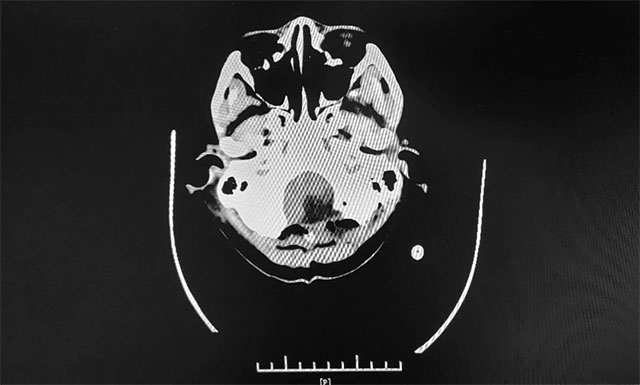

▲ 术前MR影像:左侧小脑半球及小脑蚓部占位

▲ 术后CT显示肿瘤被切除